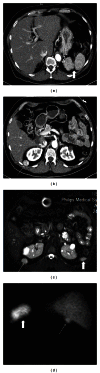

Spleen can have a wide range of anomalies including its shape, location, number, and size. Although most of these anomalies are congenital, there are also acquired types. Congenital anomalies affecting the shape of spleen are lobulations, notches, and clefts; the fusion and location anomalies of spleen are accessory spleen, splenopancreatic fusion, and wandering spleen; polysplenia can be associated with a syndrome. Splenosis and small spleen are acquired anomalies which are caused by trauma and sickle cell disease, respectively. These anomalies can be detected easily by using different imaging modalities including ultrasonography, computed tomography, magnetic resonance imaging, and also Tc-99m scintigraphy. In this pictorial essay, we review the imaging findings of these anomalies which can cause diagnostic pitfalls and be interpreted as pathologic processes.